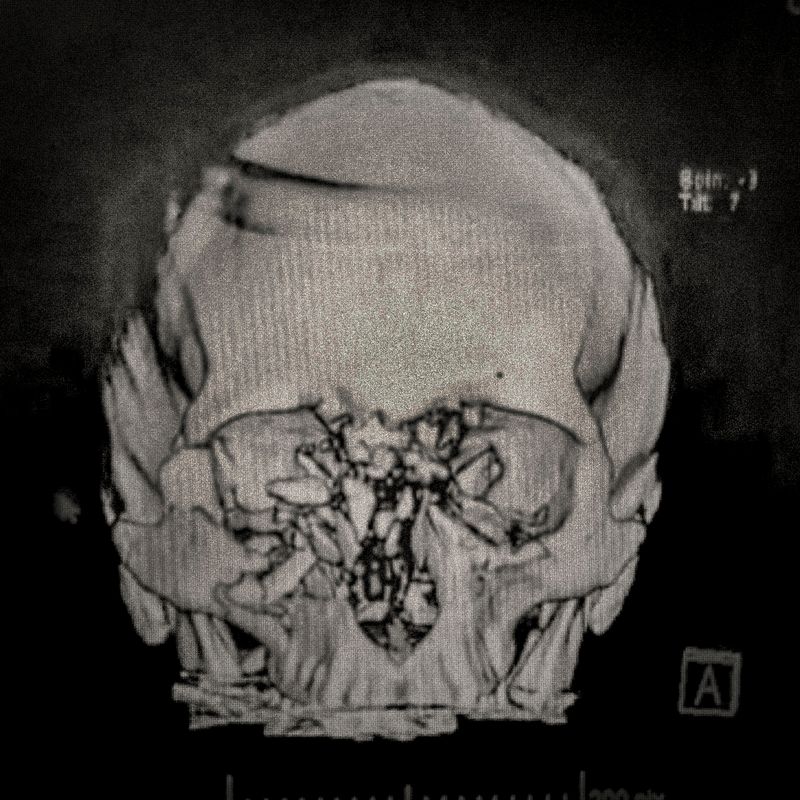

X-ray of Fabiola Campillai's face after she received a direct hit from a tear gas bomb fired by the carabineros chilean police, that caused her to lose both eyes.